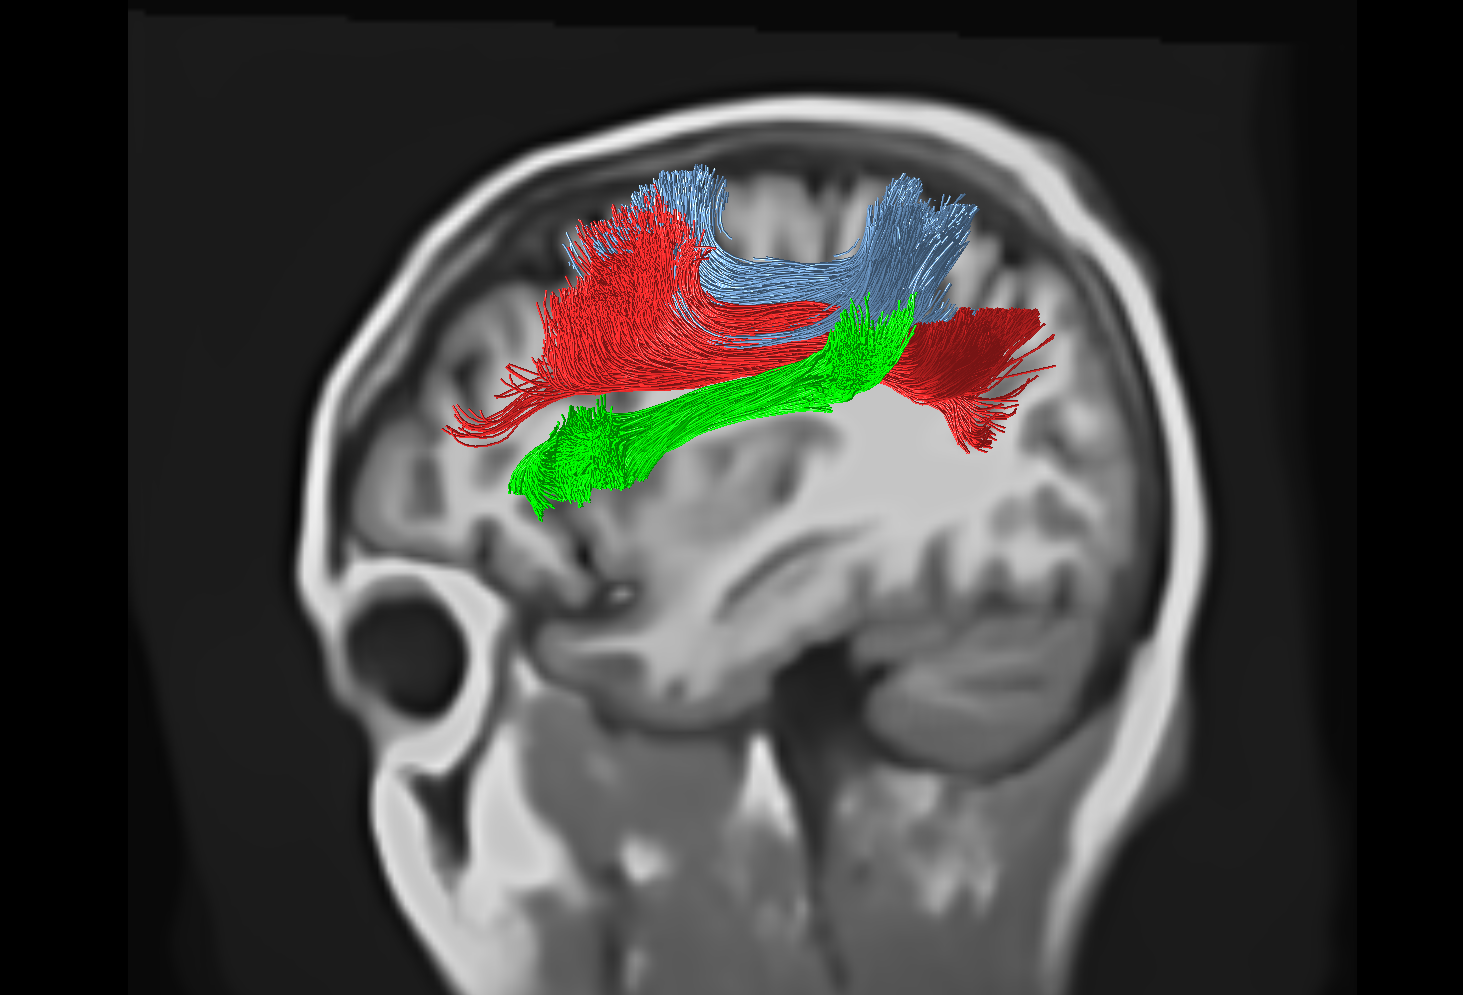

Refer to caption

Figure 8: TractSeg-derived tracking of the superior longitudinal fasciculus, reconstructing the SLF I (blue), II (red) and III (green) bundles.